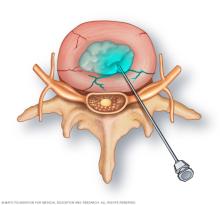

Dye injection into a spinal disk

Your healthcare team inserts the tip of a needle into the center of each disk to be examined. A contrast dye is then injected into the disk.

Your healthcare team will use an imaging technique called fluoroscopy to watch the discogram needle enter your body. Fluoroscopy allows more-precise and safer placement of the needle into the center of the disk to be examined. A contrast dye is then injected into the disk. Next, an X-ray or CT scan is taken to see if the dye spreads.